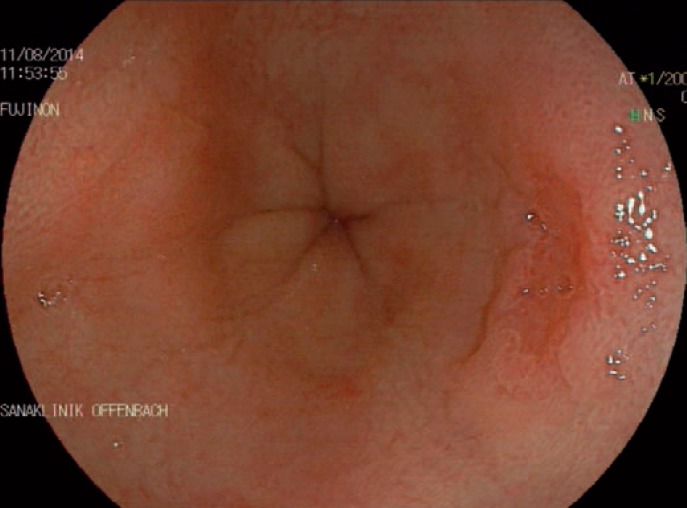

Detecting neoplastic lesions in the oesophagus can be challenging even for experienced endoscopists. Early diagnosis is essential in order to allow endoscopic therapy, which is associated with an excellent prognosis. High-definition endoscopes have a good sensitivity for diagnosing early neoplasia. Modern video chips provide an extremely high resolution (>1,000,000 pixels) and can display the mucosa and the different structures of neoplastic and non-neoplastic lesions. However, longer inspection times and greater experience on the part of the examiner are strongly associated with increased detection rates for dysplasia [11]. Barrett's metaplasia, a precancerous condition, has a reddish appearance during upper gastrointestinal endoscopy. A villous structure is the typical appearance during endoscopy (fig. 1). The full extent of all Barrett's epithelium should be described using the Prague classification [12,13]. This includes a description of the full circumferential length (C) and the maximum length (M) in centimetres. The maximum length is used to differentiate between long-segment (≥3 cm) and short-segment (<3 cm) Barrett's oesophagus. A detailed description of the intestinal metaplasia and suspicious areas it contains is important for purposes of surveillance, prognostic assessment, and subsequent endoscopic treatment. In addition to targeted biopsies of suspicious lesions, all patients with a first diagnosis of Barrett's oesophagus should undergo random four-quadrant biopsies every 2 cm (using the Seattle protocol). In case of SCC the examiner should watch out for focal areas of irregular mucosa or plaque-like lesions.

Fig. 1.

Upper gastrointestinal endoscopy of the oesophagus in a patient suffering from reflux. At the 3 o'clock position there is a small type IIc lesion highly suspicious for early adenocarcinoma.